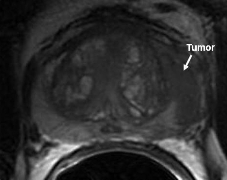

Figure 2 is biopsy proven prostate adenocarcinoma in a 62-year-old man with a Gleason grade of 6 (3+3). This example shows how functional imaging can help identify the tumor.

Figure 2c: DCE images demonstrate a focal area of abnormal enhancement in the left mid gland (solid white arrow) corresponding to the region of tumor confirmed at prostatectomy.